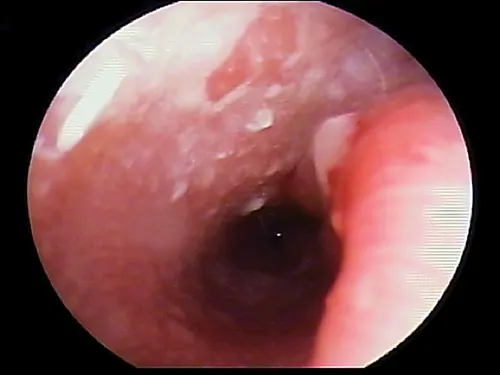

Ulceration

Ulceration of the ear canal epithelium is most often associated with a severe, chronic bacterial otitis externa (often Pseudomonas spp). The bacteria releases cytopathic enzymes resulting in ulceration (Figure 6). Tumors within the ear canal may be present and should be noted (Figure 7).

FIGURE 6

Ulceration of the ear canal. Note the disruption of the surface epithelium.